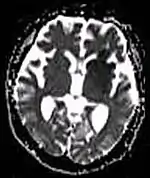

| Diffusion weighted (DWI) | Conventional | DWI | Measure of Brownian motion of water molecules.[26] | High signal within minutes of cerebral infarction (pictured).[27] | ![]() |